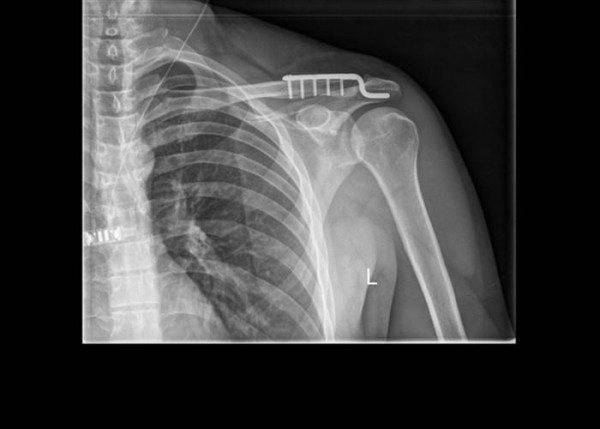

На данный момент применяется 2 типа операций – открытые и артроскопические. При открытых операциях с большим доступом применяются крючковидные пластины (см. фото 1), или конструкции, которые устанавливаются из малоинвазивного доступа (см. фото 2.3.4).